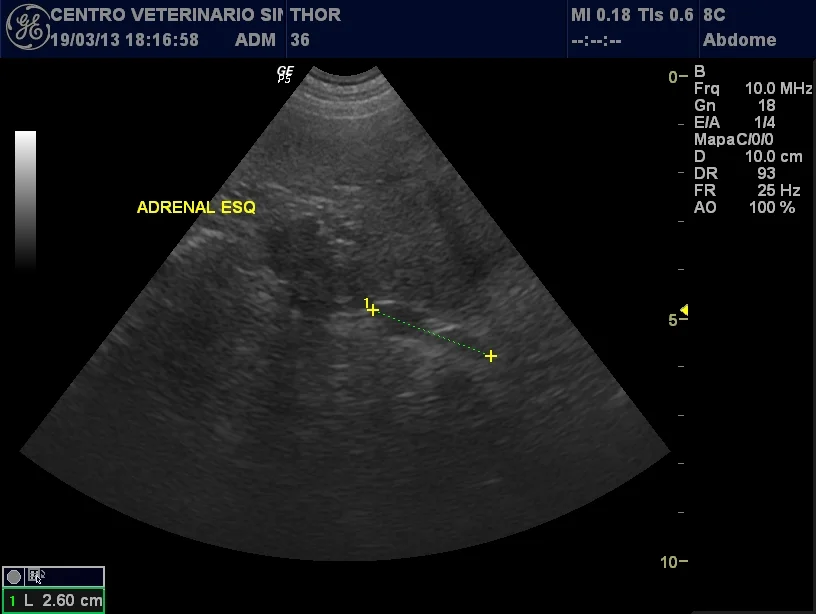

Veterinario Sintra Ecografia Abdominal Endocrinologia.jpg

Problemas endocrinológicos (hormonais) em cães e gatos podem ser encontrados no pâncreas, ocasionando diabetes mellitus ou tiróide como o hipotiroidismo, mais comum nos cães adultos e idosos, e o hipertiroidismo, mais comum em gatos idosos. Há também os casos de obesidade, muitas vezes secundários a distúrbios hormonais. Para se chegar ao diagnóstico é necessário a realização de exames de diagnóstico e laboratoriais específicos, ecografia e por vezes, outros exames mais específicos.